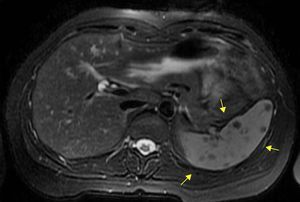

Mujer de 37 años de raza caucásica, sin antecedentes médicos de interés. Presentaba desde hacía años dolor en el epigastrio y el hipocondrio izquierdo punzante leve e intermitente diario, sin relación con la ingesta ni alteración del tránsito digestivo, con ausencia de otra sintomatología sistémica asociada. La exploración física era normal. Su estudio analítico mostró reactantes de fase aguda, frotis de sangre periférica, proteinograma y niveles de enzima convertidora de angiotensina normales; además de pruebas de autoinmunidad, serología infecciosa (incluyendo hidatidosis) y prueba de Mantoux negativos. Las radiografías de tórax y abdomen, el tránsito gastrointestinal y el electrocardiograma fueron normales. La ecografía abdominal y la tomografía computarizada toracoabdominal mostraron múltiples lesiones esplénicas de 7-9mm de diámetro sin esplenomegalia (fig. 1). La resonancia magnética abdominal mostró múltiples lesiones en el bazo, hipointensas en T2 e isointensas en T1, con realce homogéneo y tardío de contraste, con diámetro menor a 1cm (fig. 2). Ante la persistencia del dolor en hipocondrio izquierdo, así como incertidumbre diagnóstica, se decidió realizar esplenectomía laparoscópica. Macroscópicamente, el bazo presentaba múltiples nódulos externos e intraparenquimatosos de aspecto blanco-fibroso y con diámetro inferior a 1cm; negativos a pruebas microbiológicas, histológicamente compatibles con granulomas epitelioides no caseificantes (fig. 3). Tras la esplenectomía sin complicaciones, la paciente permaneció asintomática y sin tratamiento alguno en el seguimiento actual.